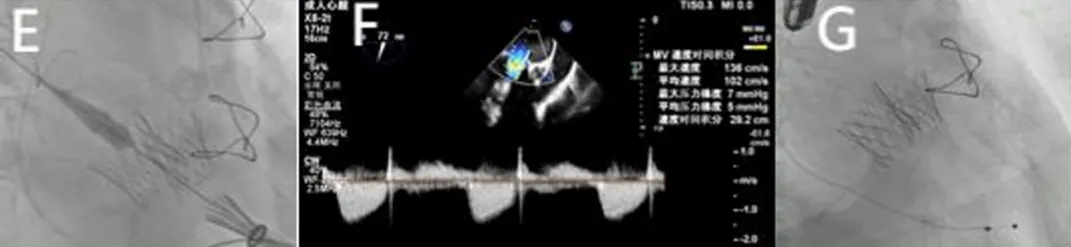

2025年6月4日,在全身麻醉下,通过TEE和荧光镜引导进行手术。通过右颈内静脉建立临时起搏。经左前外侧小切口暴露第五肋间隙,使用双重荷包缝合固定心尖;静脉注射肝素使活化凝血时间(ACT)>250秒。心尖穿刺后,先使用软导丝穿过主动脉瓣口,随后更换为Amplatz超硬导丝(波士顿科学公司)。在快速起搏(180次/分)下,使用18mm球囊对主动脉瓣生物假体进行预扩张。选择21mm ScienCrown瓣膜,旋转手柄将瓣膜从输送系统中逐步释放(视频1)。瓣膜成功植入后,无错位或瓣周漏(PVL)(图2B及视频2)。TEE显示主动脉瓣平均跨瓣压差为6mmHg,无瓣周漏(图2C及D)。随后,使用硬导丝穿过二尖瓣生物瓣进入左心房(视频3)。在快速起搏(180次/分)下于二尖瓣位置植入25mm ScienCrown瓣膜(图2E及视频4)。TEE显示二尖瓣平均跨瓣压差为5mmHg,瓣叶运动正常,无瓣周漏(图2F)。术后荧光检查显示两枚瓣膜均位置良好(图2G)。术后第一天床旁TTE显示二尖瓣压差2.52mmHg,流速0.76m/s;主动脉瓣压差13.39mmHg,流速1.7m/s,提示轻度主动脉瓣狭窄(AS)和正常二尖瓣功能(图3)。患者心功能改善至NYHA II级,并在术后第5天出院。

图2. 使用ScienCrown瓣膜进行经心尖主动脉瓣和二尖瓣ViV手术。A:18mm球囊对主动脉瓣进行预扩张。B:成功植入21mm ScienCrown瓣膜,显示无瓣周漏。C:植入后TEE确认无瓣周漏。D:术后TEE记录主动脉瓣平均跨瓣压差为6mmHg。E:二尖瓣位置25mm ScienCrown瓣膜的理想释放。F:植入后TEE评估显示二尖瓣平均跨瓣压差为5mmHg。G:术后影像学检查显示两枚植入假体瓣膜的位置及形态均正常。